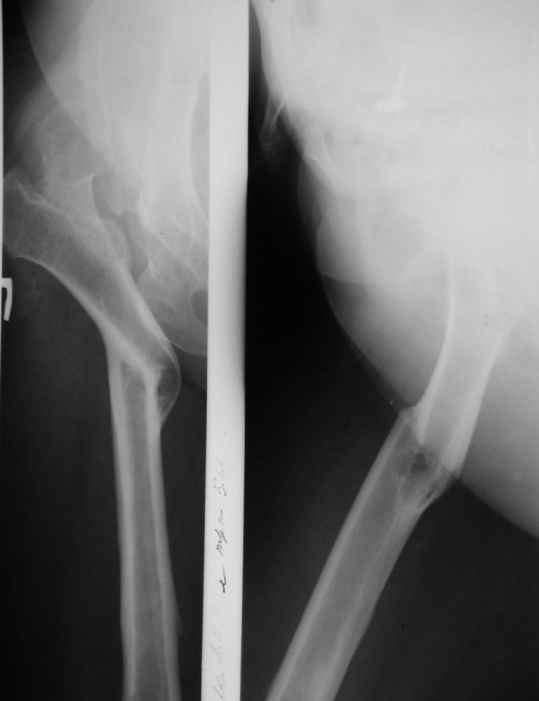

-Клиновидная остеотомия бедра на вершине деформации, с углом открыты внутрь. Это позволит выпрямить бедро, добиться полной адаптации обоих фрагментов. Использование ножки Вагнера не позволит фиксировать проксимальный отломок и потребуется какая то дополнительная фиксация, возможно пластиной.

-То же самое с использованием ножки Helios (Biomed) позволит выполнить вполне качественный остеосинтез (ножка из двух частей и позволяет оптиально зафиксировать оба фрагмента), к тому же с возможностью блокирования. Поэтому дополнительной фиксации не потребуется.

-Во всех наших наблюдениях применялась чашка Цвеймюллера.

В прищепке случай 1999 года - эндопротезирование после операции Шанца-Илизарова. Возраст пациентки 45. Коррекция была в 17 лет. А Рыков Хабаровск.